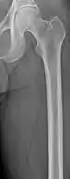

The diagnostic examination of a person with suspected multiple myeloma typically includes a skeletal survey. This is a series of X-rays of the skull, axial skeleton, and proximal long bones. Myeloma activity sometimes appears as "lytic lesions" (with local disappearance of normal bone due to resorption) or as "punched-out lesions" on the skull X-ray ("raindrop skull"). Lesions may also be sclerotic, which is seen as radiodense.[70] Overall, the radiodensity of myeloma is between −30 and 120 Hounsfield units (HU).[71] Magnetic resonance imaging is more sensitive than simple X-rays in the detection of lytic lesions, and may supersede a skeletal survey, especially when vertebral disease is suspected. Occasionally, a CT scan is performed to measure the size of soft-tissue plasmacytomas. Nuclear Medicine Bone scans are typically not of any additional value in the workup of people with myeloma (no new bone formation; lytic lesions not well visualized on nuclear bone scan).

X-ray of the forearm, with lytic lesions

Femur with multiple myeloma lesions

Same femur before myeloma lesions for comparison